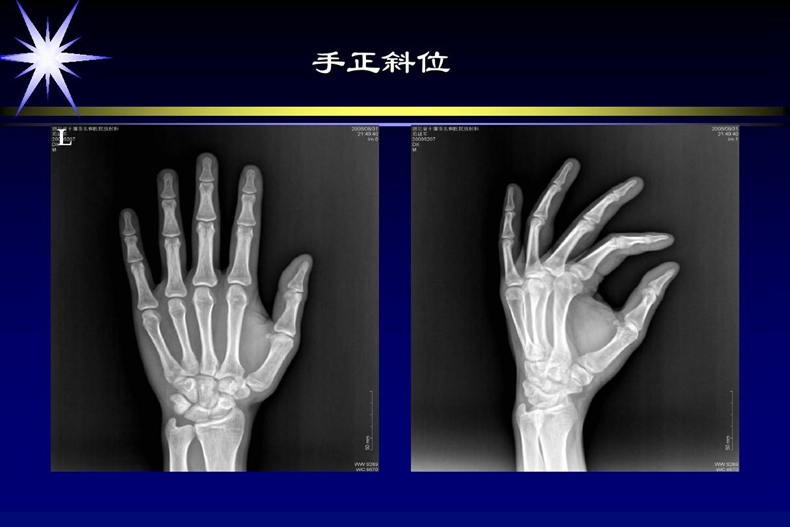

3、放射科医生

4、放射科医师

7、放射科技师